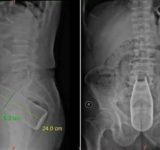

肛門に24センチの瓶が入ってしまった男性 医師「なんで入れたの?」 男性「察してください」